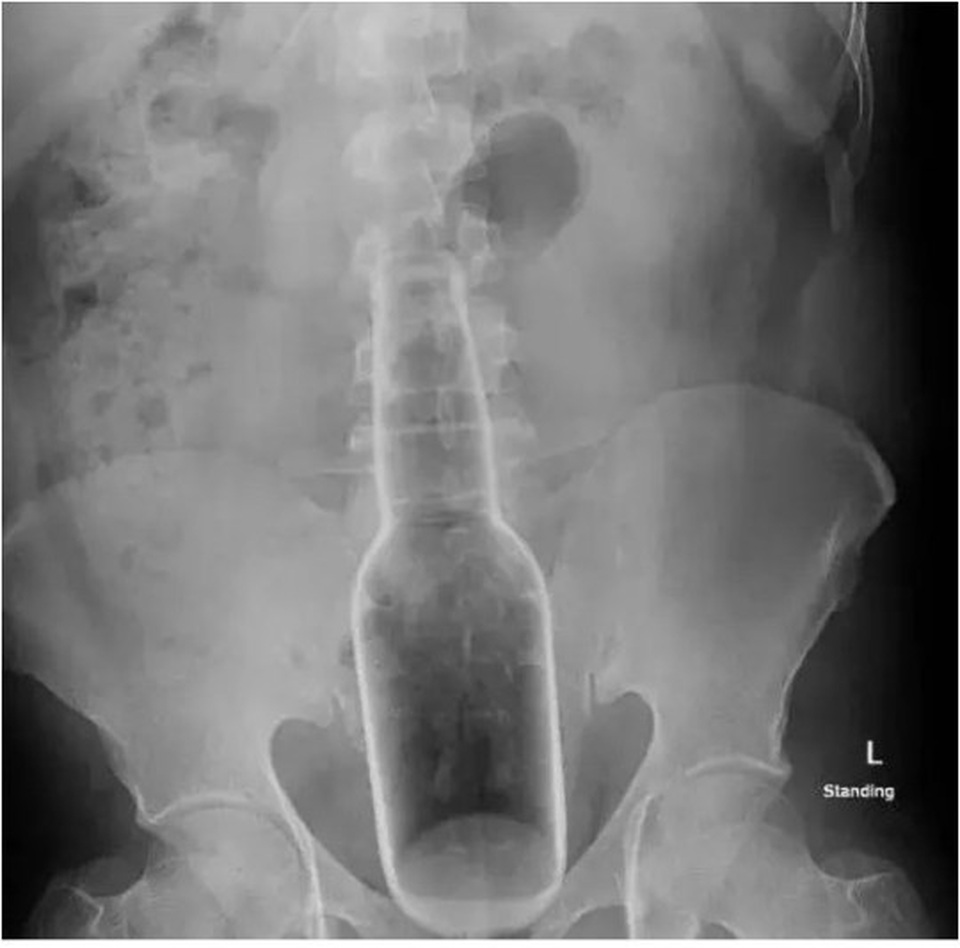

Khi vào một bệnh viện ở Quảng Đông, bệnh nhân giấu tên này khai với bác sĩ là bị đau bụng. Các kiểm tra sau đó cho thấy có 1 chai nước đường kính khoảng 5cm đang nằm gọn trong trực tràng.

Trước đó, đã có ít nhất 3 trường hợp cũng để lọt chai nước này vào trực tràng. Đây là chai được lấy ra từ bụng của 1 bệnh nhân điều trị tại bệnh viện Y học cổ truyền Dongguan.

BS Lin đã cung cấp bức ảnh chụp chai rượu nằm gọn trong trực tràng của bệnh nhân cho giới truyền thông với mong muốn cảnh báo bất cứ ai không nên có việc làm tương tự.